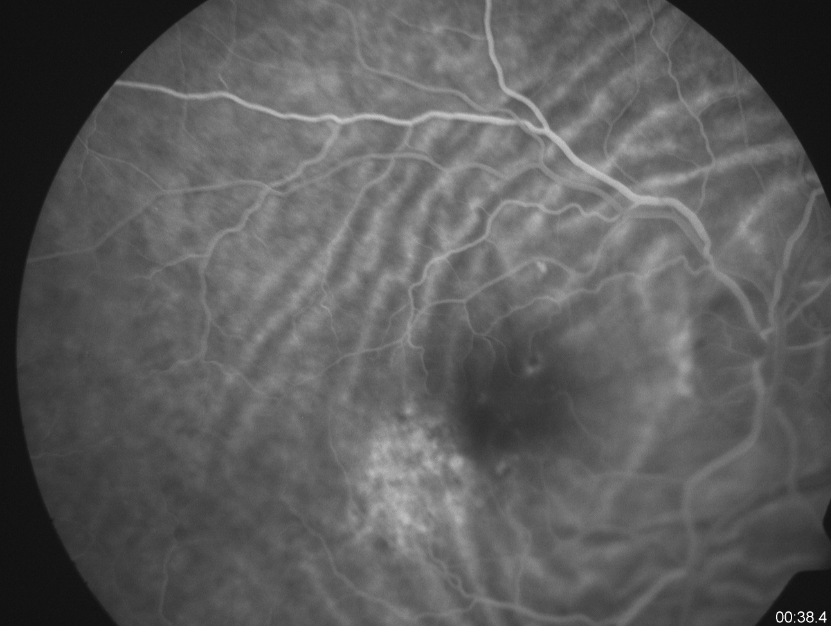

Fluorescein angiography shows an increased stippled hyperfluorescence with late staining corresponding to an area of pigmentary disturbance in the right eye. The folds are seen prominently due to their classic alternating hypo and hyperfluorescence